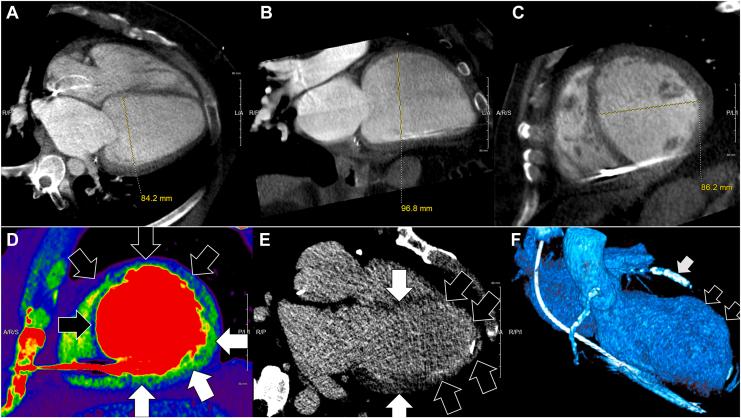

立体定向心脏射频消融术治疗高死亡风险患者室性心动过速的安全性和有效性

Safety and Efficacy of Stereotactic Cardiac Radio-Ablation for Ventricular Tachycardia in Patients at High Risk of Mortality.

CJC Open. 2025 Jan 23;7(5):545-554. doi: 10.1016/j.cjco.2025.01.015. eCollection 2025 May.

DOI:10.1016/j.cjco.2025.01.015

PMID:40433215

原文链接:https://pmc.ncbi.nlm.nih.gov/articles/PMC12105486/